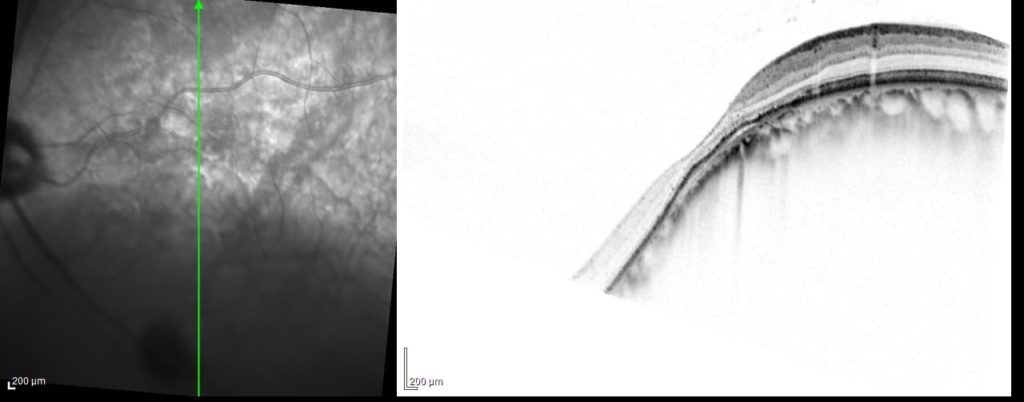

両眼ともに、後部ぶどう腫staphylomaの上縁に一致して乳頭下縁から黄斑を横断するように帯状の網脈絡膜の萎縮巣がみられる。また後部ぶどう腫領域に一致して網膜・脈絡膜が菲薄化しているため、紋理眼底tessel lated fundusがみられる。

後部ぶどう腫の上縁に漿液性網膜剥離(SRD)がみられる。この後部ぶどう腫と正常部の境界付近に脈絡膜新生血管の発生を見ることもあるため、注意が必要。